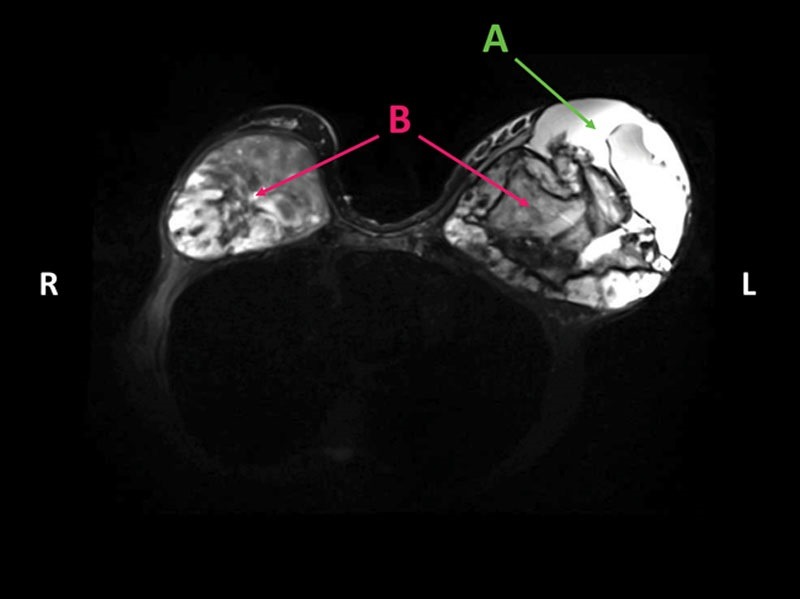

МРТ пациентки

НемедицинаМагнитно-резонансная томография молочной железы продемонстрировала большие, гетерогенные массы овальной формы в ретропекторальных пространствах, напоминающие злокачественное поражение. Визуализированы изменения соответствующие внекапсульному разрыву силиконового имплантата, простирающиеся в правую подмышечную область и верхнюю конечность. Из-за первоначального подозрения на злокачественность была проведена базовая биопсия нижней левой массы груди, которая продемонстрировала доброкачественную патологию, согласующую с организованной гематомой.